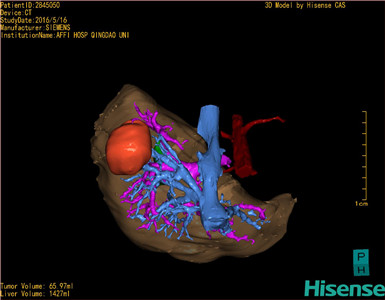

通过调节窗宽窗位调整CT序号,对肿瘤,肝实质,胆囊,下腔静脉,肿瘤,肝动脉、门静脉及肝静脉等进行三维重建;系统自动计算肿瘤体积和肝脏体积。

模拟手术操作,自动计算切除肿瘤体积。肝脏体积为1427ml,肿瘤体积为65.97ml,肿瘤体积为肝脏体积的4.6%,通过比对40-50岁正常肝脏体积为1368.38±279.24ml,通过术前模拟手术,精准判断切除后剩余肝脏体积能耐受,避免肝衰竭发生。

术前手术方案的规划。

探查见:无腹水,肝脏小结节硬化,质韧,肝Ⅵ段可触及直径5.5cm类圆形肿块,侵及肝被膜,腹腔无转移结节。决定行肝Ⅵ段切除术。断肝右三角韧带,冠状韧带,肝结肠韧带,游离右半肝。沿肝Ⅵ段边界标记预切除线,阻断第一肝门,依次钳夹、切断、结扎肝断面各结构,切除肿瘤及部分肝组织。断面渗血处分别缝合止血。松开阻断,时间36cm。于肝断面旁放置引流管1根于右侧腹穿孔引出。清点纱布器械无误,分层缝合腹壁切口。术中出血约200ml,未输血。术后血压135/75mmHg,手术顺利,麻醉满意,术后病人安返病房/综合ICU/PACU。 标本:肝Ⅵ段最大径5.5cm肿块,切缘1cm,包膜完整,无卫星灶。送病理。病理检查结果:(肝V段)肝细胞肝癌。手术时手术者可开启Hisense CAS系统手势控制功能,对肿瘤的解剖结构进行实时、全方观察、评估,起到术中导航作用。

术前三维重建:

重建图片